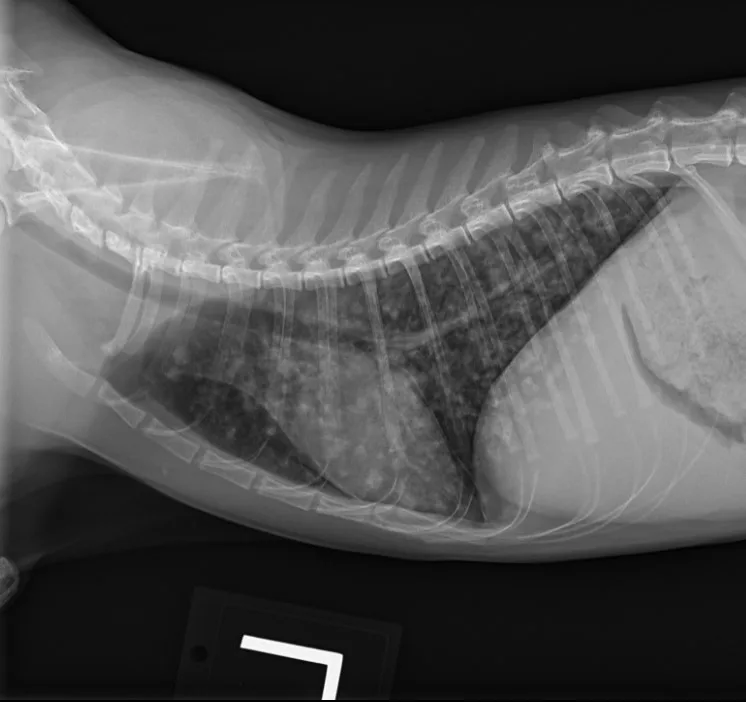

At the 1-month recheck, her weight had increased to 6 lb (3 kg); estimated BCS was 3/9. Physical examination showed a normal respiratory pattern, but increased bronchovesicular sounds were still present bilaterally. No fundic abnormalities were noted. Radiographs indicated subtle improvement of the diffuse nodular pulmonary pattern (Figure 2).

A

FIGURE 2 Left lateral (A), right lateral (B), and ventrodorsal (C) thoracic radiographs 1 month after initiation of itraconazole. Subtle improvement of the diffuse nodular pulmonary pattern can be seen.